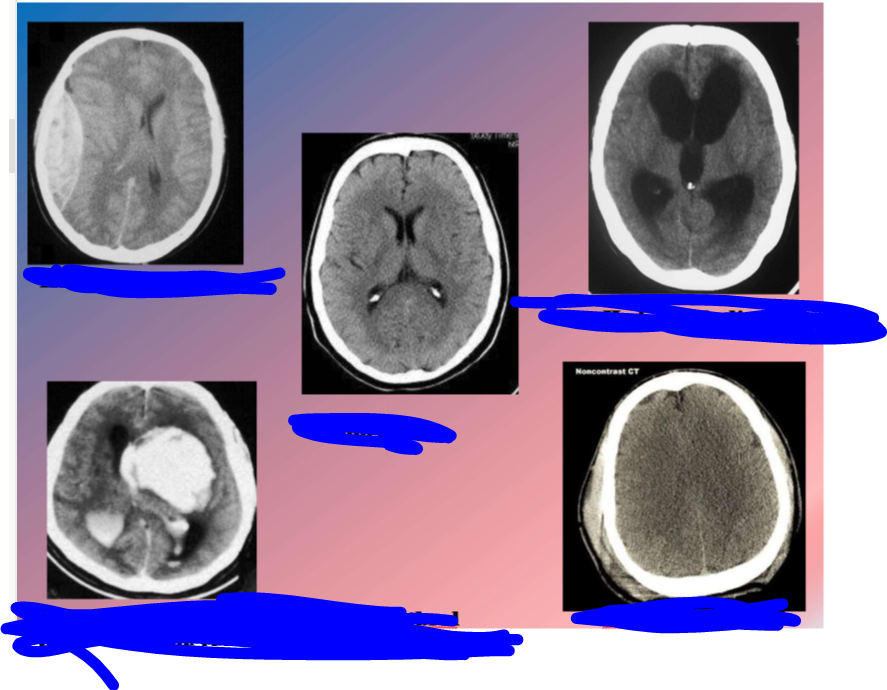

extracuri

diagnostique moi ces 5 images là

A